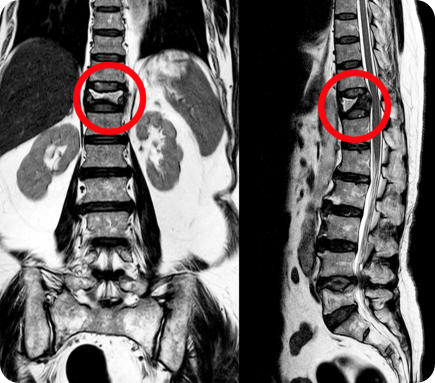

X-ray of a spine with a fracture. The fracture is circled in red.

A senior man stands straight holding a box of plants wearing gardening boots and a straw hat X-ray of a spine with a fracture. The fracture is circled in red.